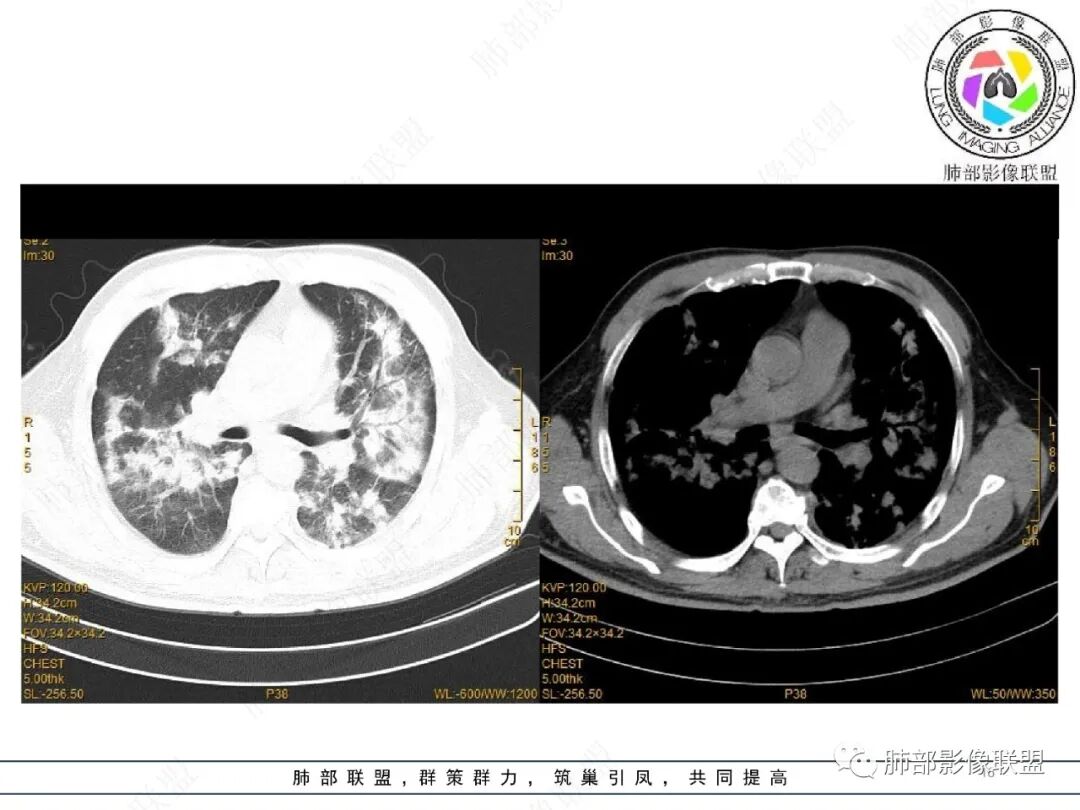

宇宙: 两肺沿支气管血管束及胸膜下分布多发结节、斑片及实变,边缘模糊,右肺病灶可见反晕,复查吸收好转,边界清,考虑OP

谢加平: 两肺叶多发斑片实变影,边缘模糊,沿支气管血管束对称分布,血管束不清,抗髓过氧化酶抗体阳性,支持血管炎表现,治疗后复查双肺病灶较前吸收好转,范围减少,病灶边缘收缩,支气管有牵拉打张,伴随0P肺炎改变。

2022.2.17CT显示两肺中内带多发结节影、斑片影、条索影,部分病灶侧向融合与胸膜平行。部分病灶沿着支气管血管束分布、其内支气管稍扩张。部分病灶呈反晕征。大部分病灶边界显示清晰,部分病灶周围可见边界不清的GGO。2022.4.12CT显示两肺中内带多发结节影、条索状、条带状高密度影,边界收缩平直凹陷,大部分病灶沿着支气管血管束分布,亦有位于胸膜下侧向融合与胸膜平行的病灶。总体与第一次CT对比两肺病灶明显吸收。